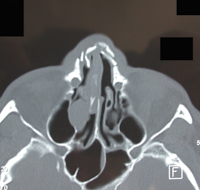

Maladie de Wegener : ulcération septale aspect scannographique